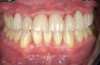

Whereas erosion is the result of chemical dissolution of tooth structure and abrasion is the loss of tooth structure caused by contact with external objects other than opposing teeth (eg, via vigorous toothbrushing), attrition is a wear process caused by direct tooth-to-tooth contact (Figure 1 and Figure 2).7 The most common cause of attrition is bruxism.8 Characterized by the involuntary gnashing, grinding, or clenching of teeth, bruxism is usually an unconscious activity, which may occur both during sleep (sleep bruxism) or when the individual is awake (awake bruxism).9-11 According to the American Dental Association, severe bruxing can cause extensive damage to the teeth and supporting structures.12

Fig 2. Right lateral view, showing severe attrition of teeth Nos. 5 though 12, abfraction lesions on teeth Nos. 6 and 11,

and overjet.

Figure 2